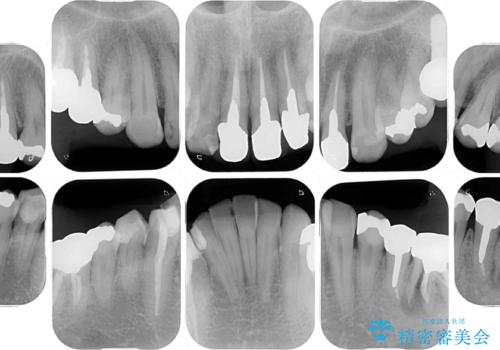

- 黄ばんだ前歯や目立つ奥歯の銀歯をきれいにしたいとのことで来院された患者様です。

欠損している歯や、割れてしまって抜歯の必要な歯などがあり、咬合力が強いため欠損部はインプラント補綴を前提に治療を行うこととしました。

しかしながら、左下の抜歯部位は骨欠損が著しく大きく、多大な垂直的骨造成を要するため、3歯を支台としたブリッジによる補綴治療とし、右下のみをインプラント補綴としました。

小さい修復物の銀歯が装着されている歯はセラミックインレーにて、その他はオールセラミッククラウンにて補綴治療を進めることとしました。